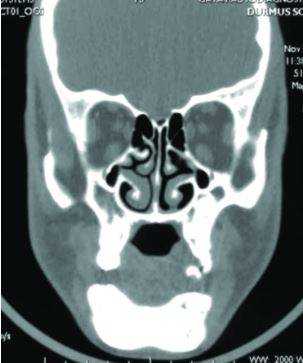

Рентген-диагностика

Прямая и боковая рентгенография челюсти способствует обнаружению опухоли в кости. Новообразование из одонтогенного клеточного материала также хорошо просматривается на рентгенограмме. При наличии опухоли снимок покажет, что зубы не контактируют с костью, а альвеолярный край имеет недостаточно четкий контур.

КТ, биопсия, другие методы диагностики

Чтобы получить представление о локации и распространении новообразования, делают компьютерную томографию челюстей. Пункционная биопсия подчелюстных лимфатических узлов и позитронно-эмиссионная томография нужна для обнаружения метастазов.

КТ челюсти и гайморовых пазух

Иногда пациент обращается к стоматологу из-за проблем с зубами, а врач назначает КТ челюсти и гайморовых пазух. Не переживайте, это не попытка навязать дополнительные обследования - часто без сканирования смежных зон просто не обойтись.

Заболевания челюсти и гайморовых (верхнечелюстных) пазух связаны с особенностями их морфологического строения. Корни зубов моляров, а иногда и премоляров (4,5,6,7 и зубы мудрости) проникают в дно пазухи. Поэтому, при возникновении проблем с зубами, это сказывается на состоянии околоносовых пазух.

КТ челюсти и придаточных пазух

То есть ЛОР-заболевания могут быть тесно связаны со стоматологическими проблемами. И иногда требуется консультация двух специалистов: и стоматолога, и оториноларинголога.

Вследствие осложнений стоматологического лечения в пазухе носа могут быть инородные тела, остатки зубов, пломбировочный материал. Если такая неприятность возникла, то не обойтись без КТ, как челюсти, так и гайморовых пазух. Потребуется комплексная терапия - одновременное лечение и зубов, и синусов. В этой ситуации КТ дает панорамную картину, позволяет оценить масштабы проблемы и позволяет специалисту составить правильное лечение.

Полученный результат рентген-снимка оценивают исключительно в одной плоскости, что не дает развернутой картины происходящего. Костные образования могут заходить друг за друга, и рентгенолог не всегда может четко отличить накладывающиеся изображения.

КТ, напротив, дает объемную трехмерную модель органа, верхнюю и нижнюю челюсть можно оценить сразу в нескольких проекциях и посмотреть даже внутреннюю структуру костей.